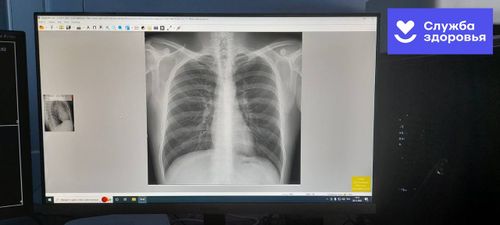

Тожуда чаа рентген аппарадын салган Ырак-узак Тожу кожуунда амгы үеге дүүштүр кылган 9 сая рубль өртектиг “Карс” деп рентген аппарады ажылдап эгелээн. 04 декабря Кадык камгалалы